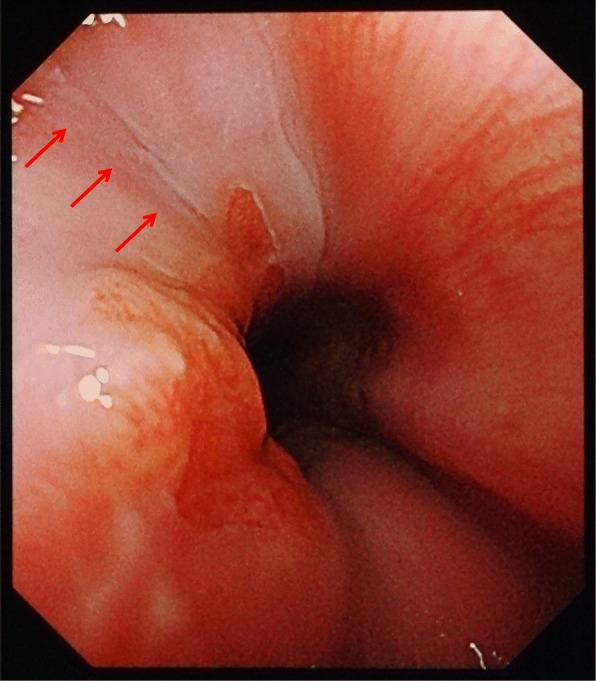

The patient in case 1 complained of severe chest pain and nausea and vomited on arrival at the hospital. He was subsequently diagnosed with Boerhaave syndrome coupled with mediastinitis using computed tomography (CT) and esophagogram. An emergency operation was successfully performed, in which a 3-cm tear was found on the left posterior wall of the distal esophagus. The patient subsequently had anastomotic leakage but was discharged 41 days later. The patient in case 2 complained of severe chest pain, nausea, vomiting, and hematemesis on arrival. He was suggested of having Boerhaave syndrome without mediastinitis on CT. The symptoms gradually disappeared after conservative treatment. Upper gastrointestinal endoscopy performed on the ninth day revealed a scar on the left wall of the distal esophagus. The patient was discharged 11 days later. In addition to the varying severity between the cases, the patient in case 2 was initially considered to have Mallory-Weiss syndrome.

病例1中的患者在入院时主诉严重胸痛、恶心并呕吐。随后通过计算机断层扫描(CT)和食管造影被诊断为Boerhaave综合征合并纵隔炎。成功进行了急诊手术,术中发现食管远端后壁有一处3厘米的撕裂口。该患者随后出现吻合口漏,但在41天后出院。病例2中的患者在入院时主诉严重胸痛、恶心、呕吐和呕血。CT检查提示其患有Boerhaave综合征但无纵隔炎。保守治疗后症状逐渐消失。在第9天进行的上消化道内镜检查显示食管远端左壁有一处瘢痕。该患者在11天后出院。除了病例之间严重程度不同外,病例2中的患者最初被认为患有马洛里-魏斯综合征。